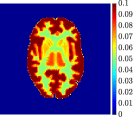

Figure 4, Figure 5, and Figure 6 show the mean images computed over the ten reconstructions obtained by the methods reg-AS-TR, reg-GN, and by the Matlab routine lsqcurvefit implementing a standard Trust-Region-Reflective least-squares algorithm [11, 10]. We used the noise-free IF and the perturbed IF with and of noise, respectively. Figure 7 contains mean and standard deviation values of the kinetic parameters computed over the ten reconstructions and over each one of the four homogeneous regions, for each one of the three noise levels on the IF.

In general, reg-AS-TR and lsqcurvefit seem to provide similar mean reconstructions, although uncertainties associated to lsqcurvefit are significantly bigger. On the other hand reg-GN seems to systematically underestimate the parameter values within region . Furthermore and as expected, for all methods the quality of the parametric reconstructions deteriorates with increasing noise levels; this is more clear from the and parametric images, probably due to the different sensitivities of the data with respect to the model parameters [37]. In reg-GN and lsqcurvefit some artifacts can be observed at the edges of the homogeneous regions, especially around region and region , whereas the effect of regularization in reg-AS-TR results in a reduced presence of artifacts while the structure of the regions is preserved. This general trend is confirmed by the error-bar plots of Figure 7. Finally, the frames in Figure 8 corresponding to reg-AS-TR show a significant improvement of the image quality with respect to what is provided by the other two approaches.